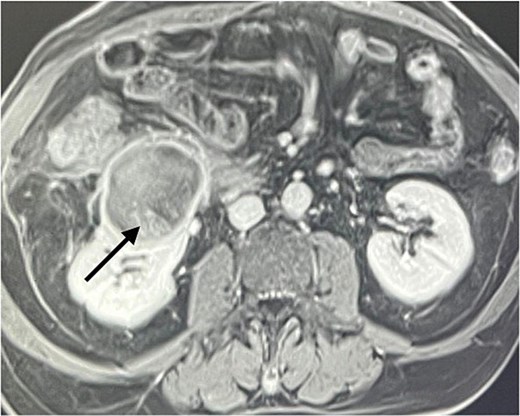

A 60-year-old male patient was referred to our clinic due to concern of infected renal cyst. Five months prior to referral, he underwent an open appendectomy and right limited hemicolectomy due to perforated appendix. At that time he was found to have accidental right Bosniak IIF renal cyst on CT scan and follow up every 6 months was recommended by urologist. Four months later, he came to emergency department with fever, chills and right flank pain. CT scan of the abdomen and pelvis with intravenous contrast was done and showed same size exophytic cyst in the lower portion of the right kidney measuring 4.9 × 5.2 cm but with new finding of rim enhancement with surrounding fat stranding suggesting complicated cyst with possible abscess formation. There was fat stranding and wall thickening of the adjacent ascending colon (Fig. 1). These findings couldn’t differentiate between infected cyst and cancer. Due to the high risk of malignancy associated with Bosniak IIF renal cyst and the challenging differential diagnosis, we further discussed the case with radiologist and decision was made to do an magnetic resonance imaging (MRI) with contrast for further evaluation and for better visualization of internal enhancement. Most MRI findings were suggestive of infected cyst. However, diffusion-weighted imaging and apparent diffusion coefficient (DWI-ADC) map showed strong internal restricted diffusion which is not specific to either abscess or tumor. Reaching the diagnosis based solely on these initial imaging findings was challenging. T1 post contrast image revealed fine internal enhancement suggesting more complex lesion than a simple infected renal cyst or abscess, raising suspicion for a neoplastic process (Figs 2 and 3).

T1 post contrast showing a ring enhancing cystic lesion in the lower pole with fine internal enhancement (arrow).